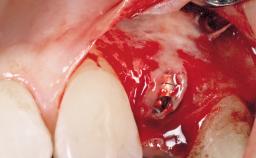

A 30-year-old female patient had lost tooth 21 and was referred to our clinic for consultation and treatment. Due to advanced apical infection, tooth 21 had been extracted two months earlier at another clinic and an acrylic-resin tooth had been bonded to the adjacent teeth. The patient desired implant treatment to avoid any damage to the adjacent natural teeth. While the patient had no history of any systemic disorder, she was a heavy smoker and exhibited medium to advanced periodontitis in the entire jaw. After the initial treatment to achieve a pocket probing depth of less than 4 mm and no bleeding on probing, a decrease in the height of the papillae mesial and distal to the extraction site and overall gingival recession were observed.

Bone Augmentation Horizontal|Staged

Augmentation Materials Autogenous chips|Membrane

Soft Tissue Grafting Simultaneous